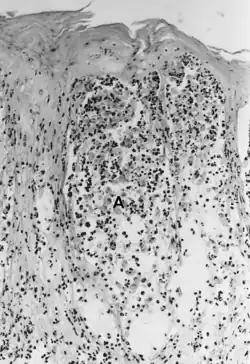

Foot-and-mouth disease - acantholysis in a sample of a skin vesicle: Necrosis of the stratum spinosum can be observed, and keratinocytes floating in the vesicular fluid (spongiosa).

Acantholysis is the loss of intercellular connections, such as desmosomes, resulting in loss of cohesion between keratinocytes,[1] seen in diseases such as pemphigus vulgaris, Grover’s disease, and Hailey-Hailey Disease.[2][3] It is absent in bullous pemphigoid, making it useful for differential diagnosis. This disruption between cells causes intra-epidermal clefts, vesicles and bullae due to cells becoming rounded and no longer attached to one another.[4]